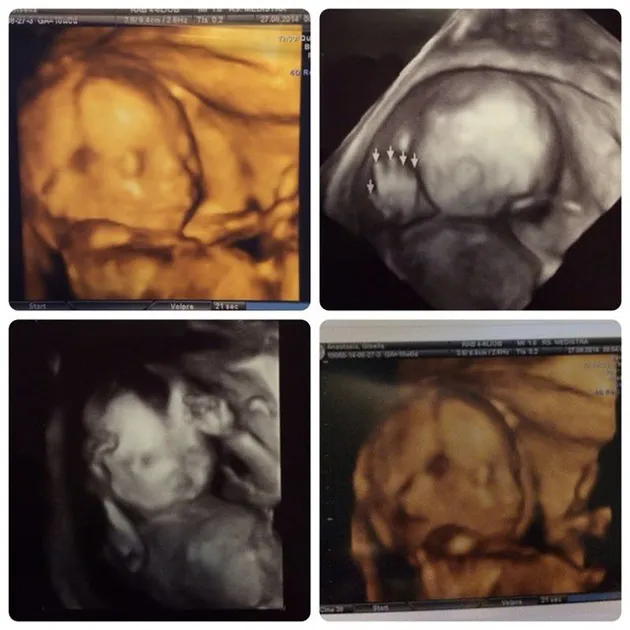

Inilah dia baby G yang kini tengah ditunggu-tunggu Gading dan Gisel. Bahagianya!

Hak Cipta: Gisel Official Instagram